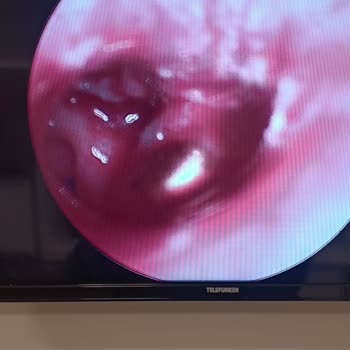

05.11.2025 tarihinde saat 15:30 civarında 11 aylık bebeğimi ishal ve kusma şikayetiyle Mersin Üniversitesi Hastanesi Çocuk Acil bölümüne götürdüm. İlk başta röntgen istediler, bu süreçte kapalı, yeşil gözlü bir hemşire bana çok yardımcı oldu ve kendisine minnettarım. Ancak röntgen sonrası danışmaya ...